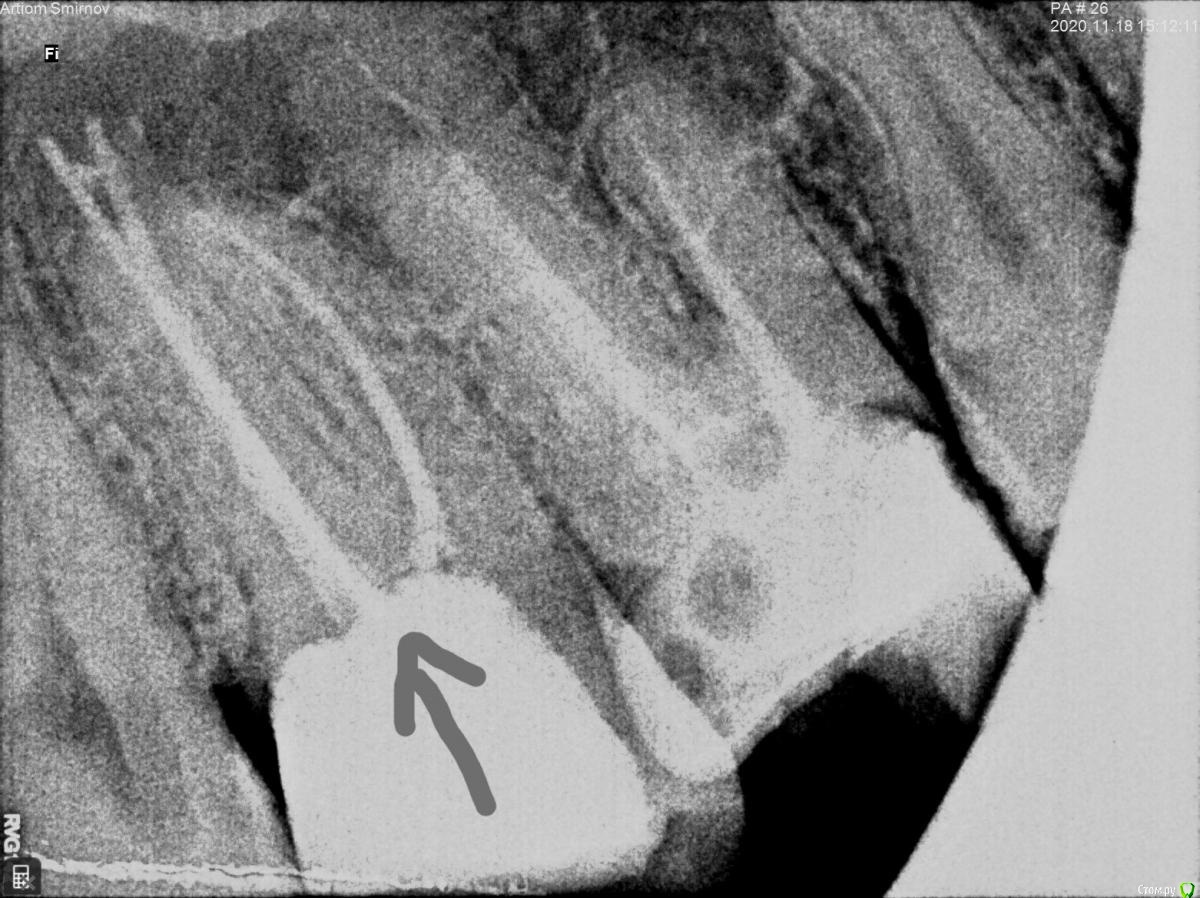

Artiom_Kl Опубликовано 26 ноября, 2020 Поделиться Опубликовано 26 ноября, 2020 Доброго времени суток! Буду очень Вам признателен, если дадите совет. Ситуация такова: Стоматолог запломбировал 3 канала и поставил временную пломбу (на месяц, до следующего приема, когда он должен уже поставить постоянную пломбу). Однако уже 3 недели, как я испытываю практически постоянный дискомфорт в зубе, который на 2 неделе уже перерос в ноющую боль, хоть и незначительную и не постоянную (сейчас уже 3 неделя-ситуация без изменений). Обратился к стоматологу. Он посмотрел визуально ротовую полость и сказал, что всё нормально, боль какое-то время может быть. И, по его словам, после установки постоянной пломбы боль через некоторое время должна исчезнуть. Нерв, как он добавил, беспокоить не может, так как он его умертвил. Однако меня терзают сомнения, что каналы запломбированы качественно. Я запросил у него снимки, сделанные после пломбирования каналов. Взгляните, пожалуйста, на рентгеновские снимки. Можно ли по ним судить о качестве пломбирования каналов ? Ссылка на комментарий